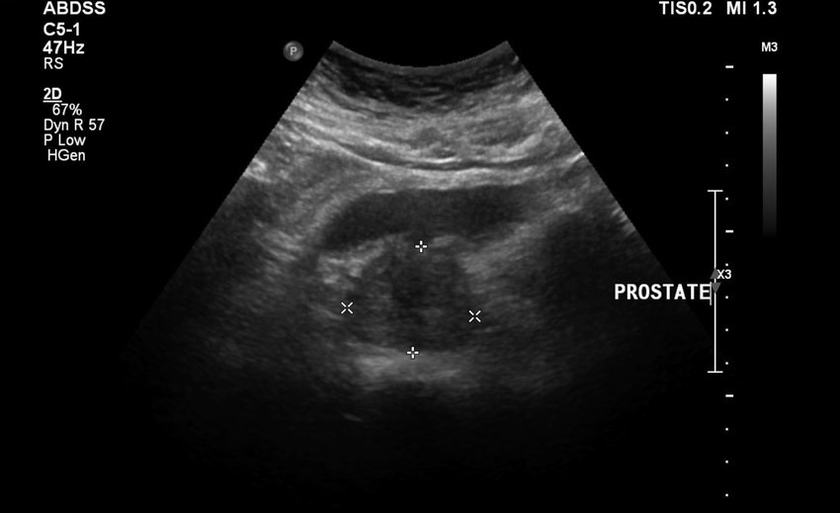

Niso pustili, da se gumirani živijo mirno, nato pa so dodali bolečine v spodnjem delu hrbta, testi in rezultati ultrazvoka so bili slabi. Dobesedno se je bilo nemogoče odmakniti od stranišča, v dimljah in nenehnih bolečinah je bil občutek teže. Predpisana je bila neposredna masaža prostate, ki me je potopila v paniko. Začel je iskati druge, manj travmatične metode zdravljenja.